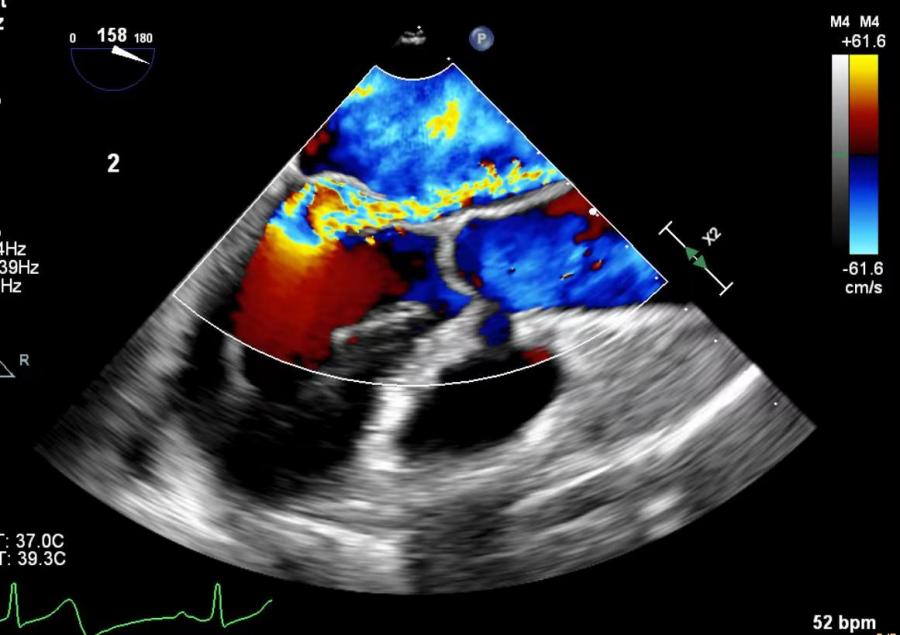

术前食道超声示二尖瓣大量偏心反流

术前食道超声示二尖瓣大量偏心反流,腱索断裂伴后瓣脱垂